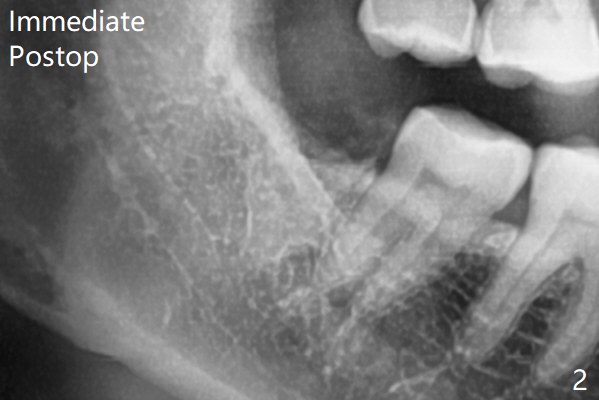

术前外斜脊(图一:*)存在,术后即刻没有消失,放置0.5毫升骨水泥(图二)。